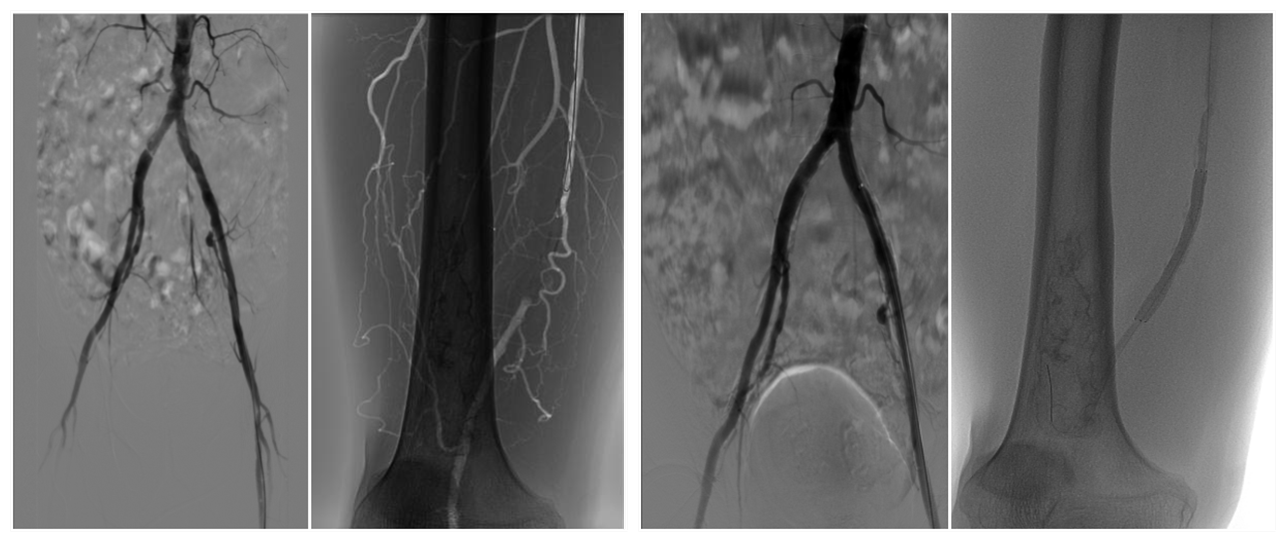

手术由介入与血管外科张喜成主任医师及顾铖涛住院医师配合实施,仅用一个半小时,便成功开通血管,植入两枚支架,顺利完成手术。术后患者下肢发凉、麻木,疼痛即缓解,术后第一天即下床活动。

(术前造影) (植入支架后造影)